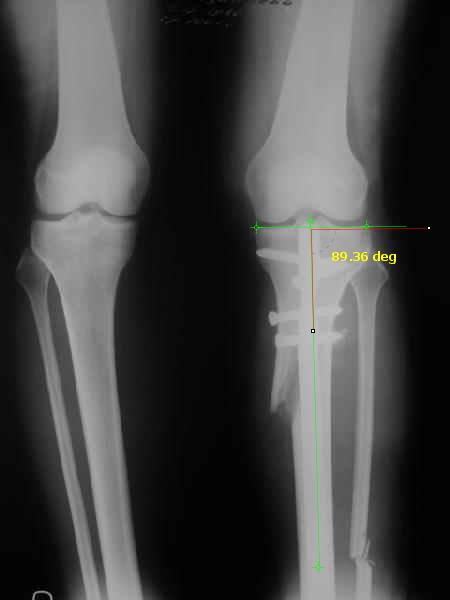

It is very interesting to me that as you have derotated the tibia you have centred the patella, I think and the prox tibia looks much more anatomic.

The analysis in the attached images is direct, just using the tools.

Tibial tilt is perhaps more than you want but the tibial correction is to 90 (very slight over

correction.

Will need full length views to tell us about the hka but it appears neutral.